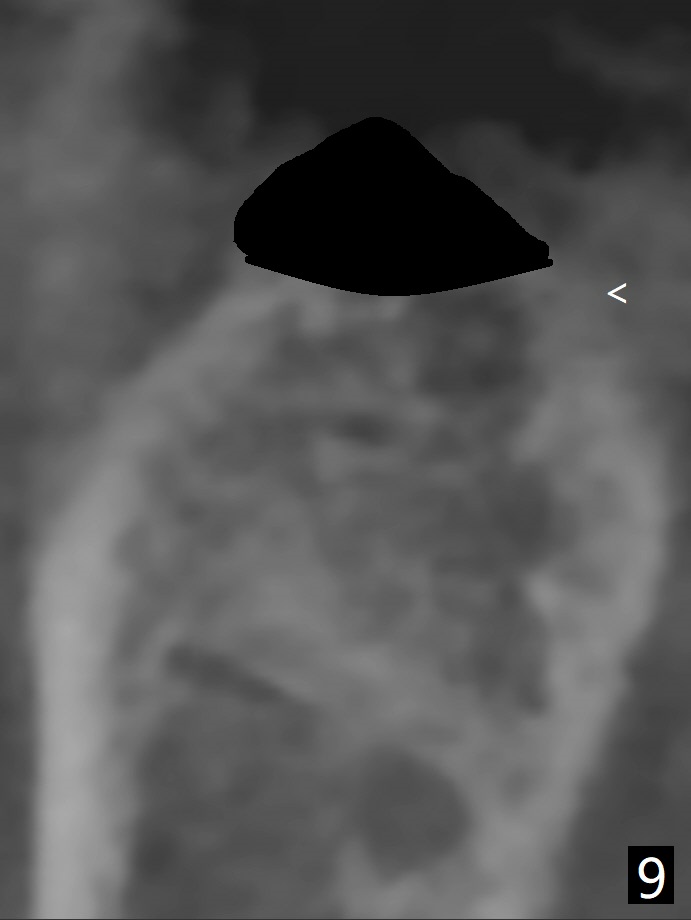

A 61-year-old woman with history of bruxism returns to clinic with chief complaint "I cannot chew bottom right. Top left has had pain and swelling before". Exam shows loose FPD at #31 (Fig.1) and necrosis of #14 (Fig.2). When the FPD is sectioned, the tooth #31 is found to have subgingival caries, filled with IRM (Fig.3). CT shows large PARL around MB and P roots of the tooth #14 (Fig.4), the fractured distal root of the tooth #19 with the low buccal plate (Fig.5) and a 5x10 mm implant being able to be placed at #30 (Fig.6). The crestal cortex (Fig.7 arrowheads) is thin in the edentulous area for several decades. The bone density is low (Fig.8, underprep). To place an implant over the pointed ridge, it should be trimmed prior to osteotomy (Fig.9). The bone loss associated with the fractured distal root is severe at #19 (Fig.10). After removal of the mesial root (Fig.11: 1), perform distal socket shield (2).